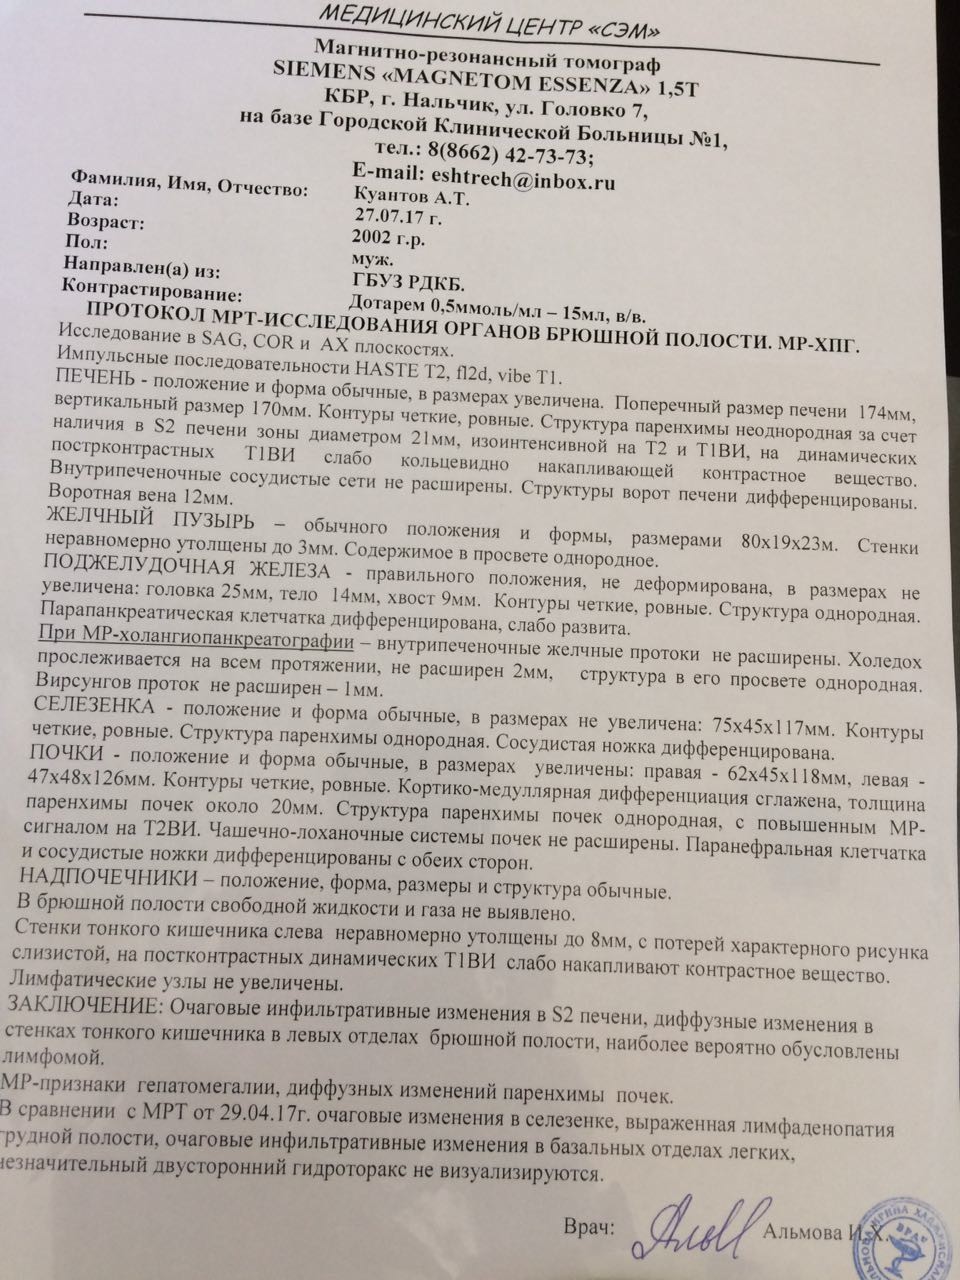

УЗИ лимфоузлов при лимфоме Ходжкина

Раздел: Образы вокруг